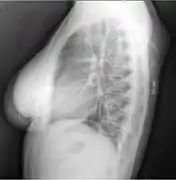

A physical exam is typically the easiest way to diagnose it. Rarely, a tissue biopsy or imaging may be required. The imaging modality of choice is magnetic resonance imaging (MRI) because it has superior sensitivity of distinguishing it from liposarcoma as well as mapping the surrounding anatomy.[22]